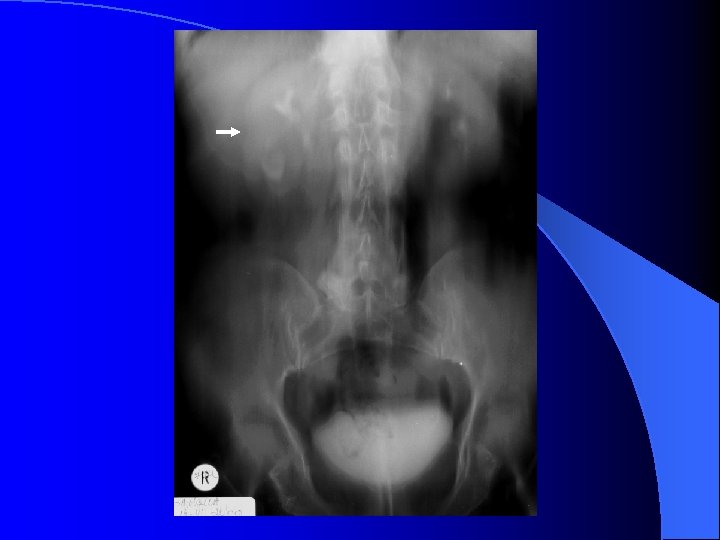

UIV - modificări funcţionale Secreţie (perfuzie) – nefrogramă întârziată, asimetrică – nefrogramă persistentă l Excreţie – urogramă l – întârziată – contrast absent în căile excretorii la 5 min. – asimetrică – opacifiere mai redusă a unui SPC (excreţie tardivă) – rinichi mut urografic – contrast absent în căile excretorii a unui SPC după eliminarea substanţei de contrast prin rinichiul normal l Cauze – prerenale: ischemie funcţională/organică – renale: inflamaţii acute/cronice – postrenale: sindrom obstructiv

Modificări morfologice – căi excretorii - dimensiuni l Dilataţia l – creştere de diametru/volum SPC – dilataţie globală = hidronefroză – calice: contur extern drept/convex – tije caliceale: diametru crescut – bazinet: contur inferior convex Ureter – asociază dilataţie SPC = ureterohidronefoză l Vezică urinară – apreciată prin rezidiul postmicţional l – obstrucţie acută – contururi neregulate (“vezica de luptă”) – obstrucţie cronică – volum > 500 ml l Cauze – sindromul obstructiv

Modificări morfologice – căi excretorii Lacuna – transparenţă în interiorul căii excretorii opacifiate – contur – regulat, net ~ benign – neregulat, şters ~ malign l Cauze l – litiaza radiotransparentă – tumori uroteliale maligne/benigne – cheaguri sanguine